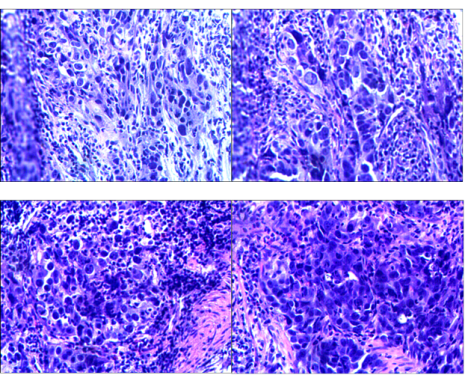

肿瘤分子病理:

胃癌标本FISH检测:HER2(扩增)

图3 FISH检测

免疫组化(VENTANA全自动化学染色):MLH1(-内对照+);MSH(+);MSH6(+);PMS2(-内对照+);EBER(-)。

图4 免疫组化(左:PMS2   右:EBER)